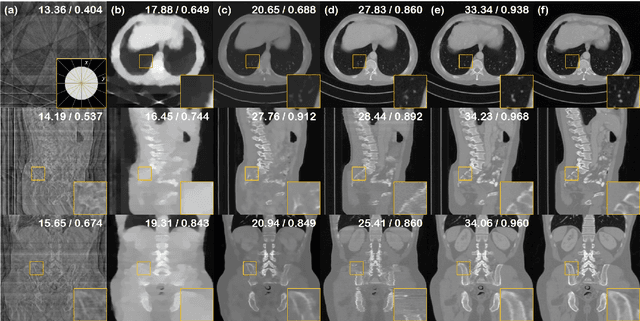

Abstract:Recently, diffusion models have been used to solve various inverse problems in an unsupervised manner with appropriate modifications to the sampling process. However, the current solvers, which recursively apply a reverse diffusion step followed by a measurement consistency step, often produce sub-optimal results. By studying the generative sampling path, here we show that current solvers throw the sample path off the data manifold, and hence the error accumulates. To address this, we propose an additional correction term inspired by the manifold constraint, which can be used synergistically with the previous solvers to make the iterations close to the manifold. The proposed manifold constraint is straightforward to implement within a few lines of code, yet boosts the performance by a surprisingly large margin. With extensive experiments, we show that our method is superior to the previous methods both theoretically and empirically, producing promising results in many applications such as image inpainting, colorization, and sparse-view computed tomography.